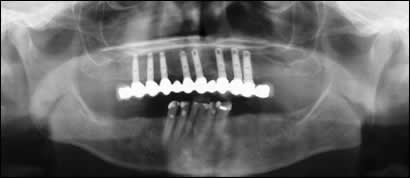

Fig 6: The post-operative radiograph reveals the successful integration of eight dental implants and the 12 unit porcelain bridge.